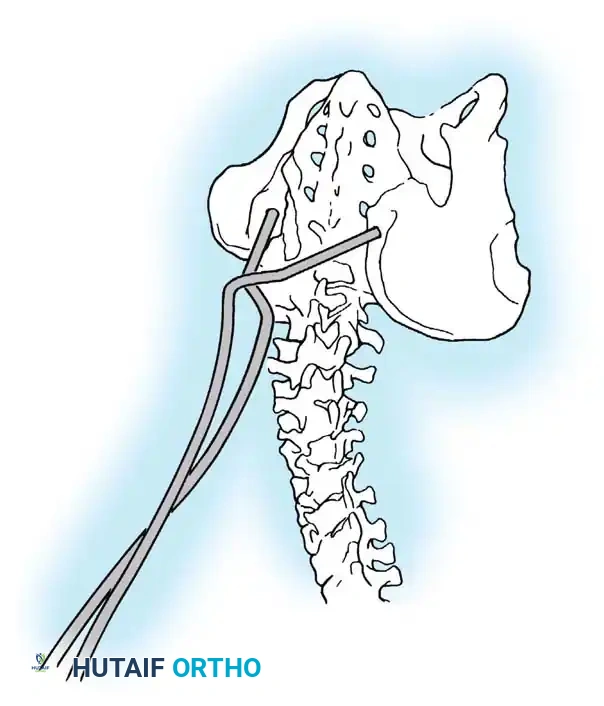

Determining Fusion Levels

Neuromuscular curves require significantly longer fusions than idiopathic curves.

* Proximal Extent: Fusion should routinely extend to T4 or higher. Stopping at or below T4 carries a high risk of cephalad progression of the deformity ("adding on") and subsequent proximal junctional kyphosis (PJK).

* Distal Extent: The decision to fuse to the sacrum/pelvis is critical.

* Excluding the Sacrum: Can be considered in ambulatory patients who require lumbosacral motion, possess no significant pelvic obliquity, and demonstrate a horizontal L5 vertebral body.

* Including the Pelvis: Mandatory for nonambulators with fixed spinopelvic obliquity. If bending or traction films reveal more than 10 to 15 degrees of L4 or L5 tilt relative to the interiliac crest line, the fusion must extend to the pelvis.

Image

Maintaining physiological lumbar lordosis is paramount in insensate patients fused to the pelvis. Proper sagittal alignment distributes body weight equally beneath the ischial tuberosities and posterior thighs, drastically reducing the risk of pressure sores over the coccyx and sacrum.